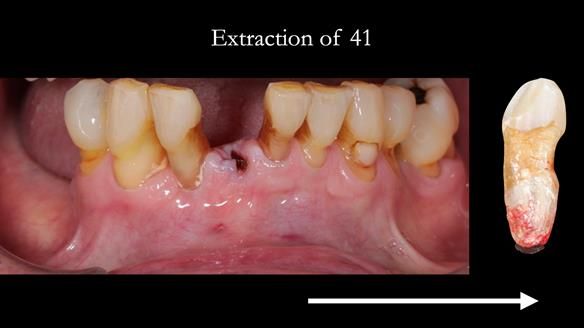

- Missing teeth on the lower right side. This makes the upper denture tip when chewing and biting.

- The remaining lower 9 teeth had periodontal disease. Syed Abad, Specialist in Periodontics at the practice managed it.